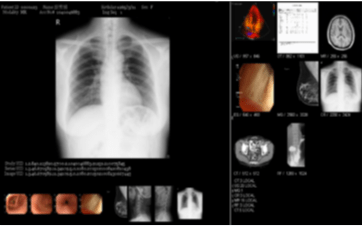

醫學影像系統

捷格科技醫療影像傳管系統 ImageSVR PACS system 支援各種類醫療影像設備, 包括CT, MR, MRI, Mamo, Echo, 核醫, 正子造影...等, 於2008年獲得美國 FDA 510k Class II 第二級醫材認證。

臨床圖像系統

除了醫學影像之外,許多的臨床工作也會透過方便的手機或平板電腦拍下數位照片佐證,捷格推出的臨床影像系統支援Android, iOS系統,並且具備完整後台機制,方便醫師管理與取用。